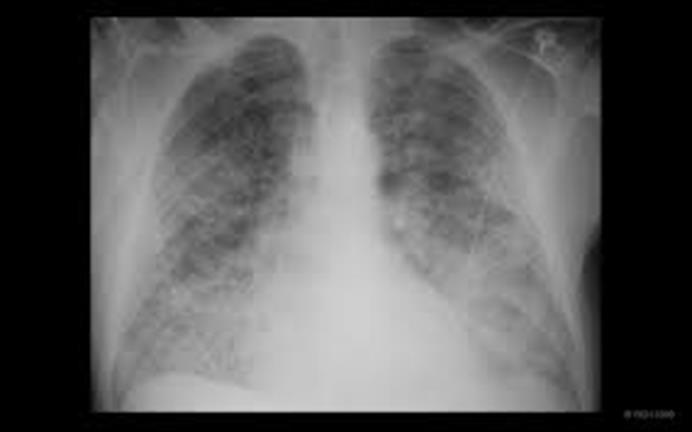

امروز دومین روز بستری آقای قربانی  در بخش است و شما به عنوان کارآموز مسوول بیمار جهت ویزیت بر بالین وی حاضر می شوید. شرح حال روز اول را که توسط خودتان به عنوان کارآموز بیمار در پرونده تکمیل شده در فایل زیر ملاحظه می کنید.

امروز طی مصاحبه با بیمار و بررسی پرونده اطلاعات زیر  را بدست می آورید.

تنگی نفسم تا حدی بهتر شده طوری که دیشب توانستم بخوابم، البته هنوز نمیتونم طاق باز بخوابم ولی مدتهاست همین طوری هستم، ورم پام کمتر شده و مشکل جدیدی نداشتم از دیروز.

معاینات جدید:

بیمار کمی تاکی پنه دارند اما دیسترس واضح ندارند . علایم حیاتی:

BP=140/80, PR=80, T=36.5, RR=23, O2sat in room air: 95%

در سایر معاینات : JVP برجسته، ادم کمتر شده، رال خفیف در قواعد ریه، سوفل سیستولیک 3/6 در اپکس دارند .

پاراکلینیک آماده شده:

WBC=8800 (PMN:60%, L:40%), Hb= 14, MCV=80, PLT=300000

Cr=0.9, Urea=35, K=3,6, Na=138

Troponin: negative

Pro BNP=4500 (<450)

داروهای تجویز شده از روز قبل:

Drip Lasix 6 mg/h

Tab ASA 80 mg/daily

Tab Pantoprazole 40 mg/daily

Tab Losartan 25 mg/BID

Tab Atorvastatin 40 mg /daily